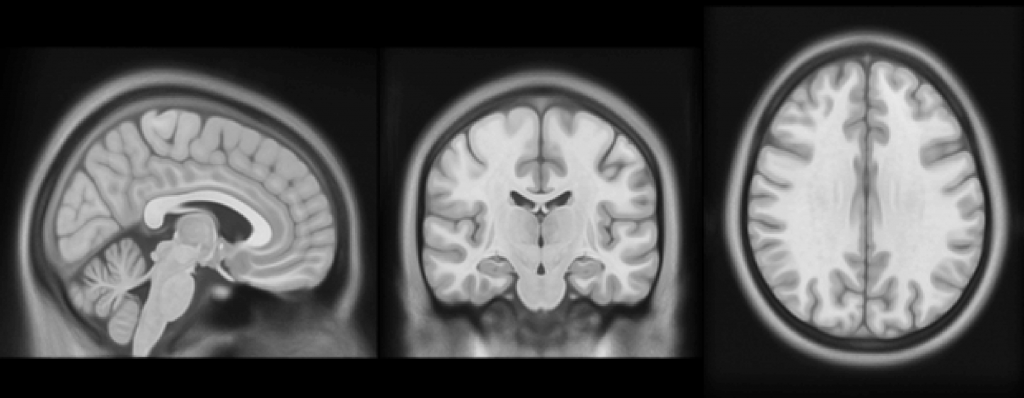

– Nowością jest fakt, że badania były prowadzone w sposób podłużny, czyli każdy uczestnik badania był skanowany trzykrotnie – wyspany, po zarwanej nocy i po pięciu dniach niewystarczająco długiego snu, około pięciu godzin na dobę. Korzystaliśmy z rezonansu magnetycznego – przy jego użyciu skanowaliśmy mózg. Mogliśmy dzięki temu spojrzeć zarówno na jego anatomię, jak i funkcjonowanie. Do analizy tych danych wykorzystaliśmy teorię grafów, dzięki czemu udało nam się szczegółowo zmapować sieć połączeń funkcjonalnych w mózgu  – tłumaczy Patrycja Ściślewska.

Wskutek niedoboru snu upośledzeniu ulegają funkcjonalne połączenia między obszarami mózgu. W szczególności wrażliwe są tzw. „huby” – obszary mózgu, które charakteryzują się największą liczbą połączeń. Mózg kompensuje sobie utratę połączeń, tworząc nowe drogi przepływu informacji. Wykorzystując uczenie maszynowe, naukowcy potrafią rozpoznać, czy dany obraz połączeń w mózgu należy do osoby chronicznie niewyspanej, czy do osoby, która zarwała noc.